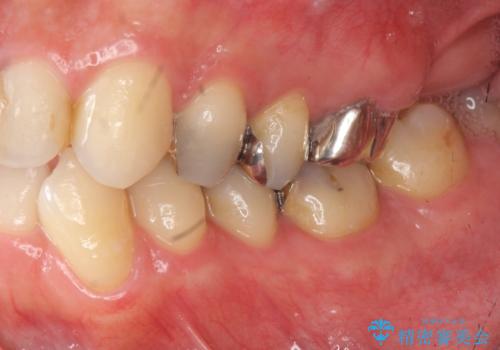

- 突き出た前歯の角度の改善と虫歯治療の改善を求めて来院されました。

虫歯を除去したのち、マウスピース矯正治療を行い、歯並びやがたつきを改善したのち、セラミックに置き換えることで審美性の向上を計画します。